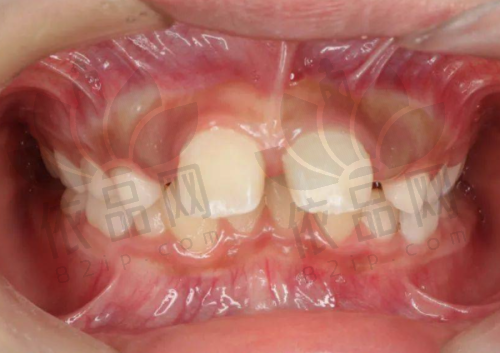

在牙齿矫正方面,无论是轻度牙列不齐,还是复杂的咬合问题,他都能根据患者的牙齿结构给出合适的矫正方案,使牙齿修复美观与正常功能。另外,在儿童齿科方面,罗春雨医生也积累了一定的经验,能够耐心与小朋友沟通,减少就诊时的抵触情绪,从而顺利完成诊疗操作。

在牙齿修复方面,他注重牙齿色彩和形态的协调度,采取分层比色、模型调试、微创处理等方式,提升整体美观程度;在牙齿矫正治疗中,他根据每位患者的口腔条件进行数字化方案设计,使整个矫正过程更加精细效率高;儿童治疗部分,他注重心理疏导技巧,以游戏方式引导配合操作,提升儿童配合度。

有患者反馈,罗医生在儿童牙科方面非常有耐心,即便小朋友哭闹也能安抚情绪,整个治疗过程比较顺利;也有成人患者表示,之前去多家医院治疗牙病恐惧感强,而在罗医生的引导和贴心服务下,成功完成了多项诊疗操作。